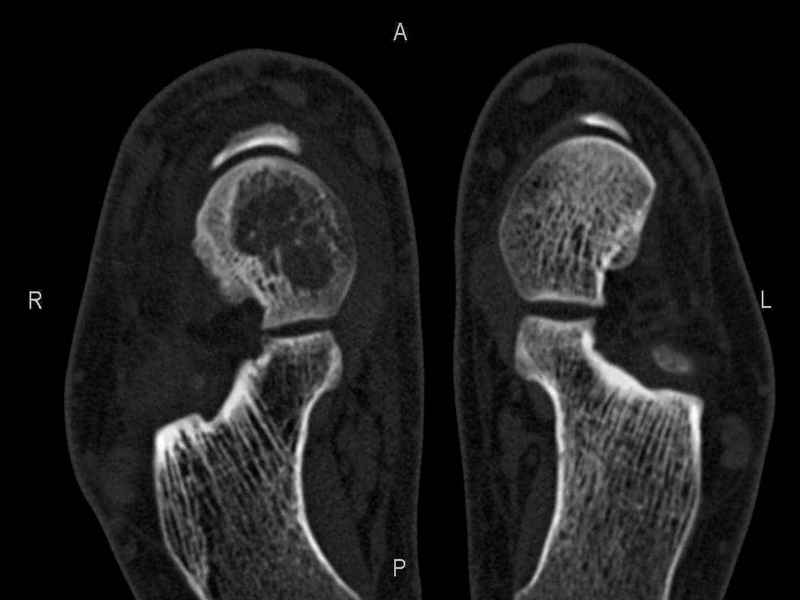

Уважаемые коллеги, обратился за помощью пациент, мужчина, 25 лет. С жалобами на болевой

синдром в области голеностопного сустава и среднем отделе стопы. Травму отрицает. Со слов,

болевой синдром в течении 1 года. Последние 1-1.5 мес периодически вынужден пользоваться

костылями. После ограничения нагрузки боли уменьшаются. Соматически здоров. До появления

болей активно занимался рукопашным боем.

На СКТ картина рассекающего остеохондрита блока

таранной кости, киста шейки таранной кости с признаками импрессии суставной поверхности. А

также - разрастания переднего края б\берцовой кости сопровождающиеся клиникой импиджмент

синдрома.